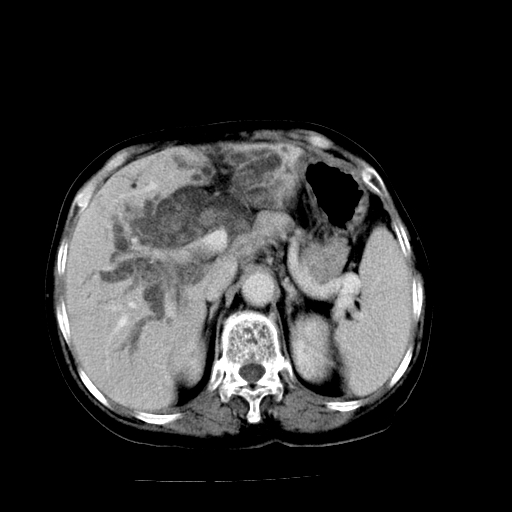

以下是引用卜一在2009-4-7 5:06:00的发言:[br]左右肝内胆管结石伴扩张合并胆系感染;不除外胆管细胞癌可能。支持! [br] [br]

以下是引用随光逐影在2009-4-7 8:21:00的发言:[br]肝内外胆管多发性结石并肝内外胆管扩张;胆系感染。